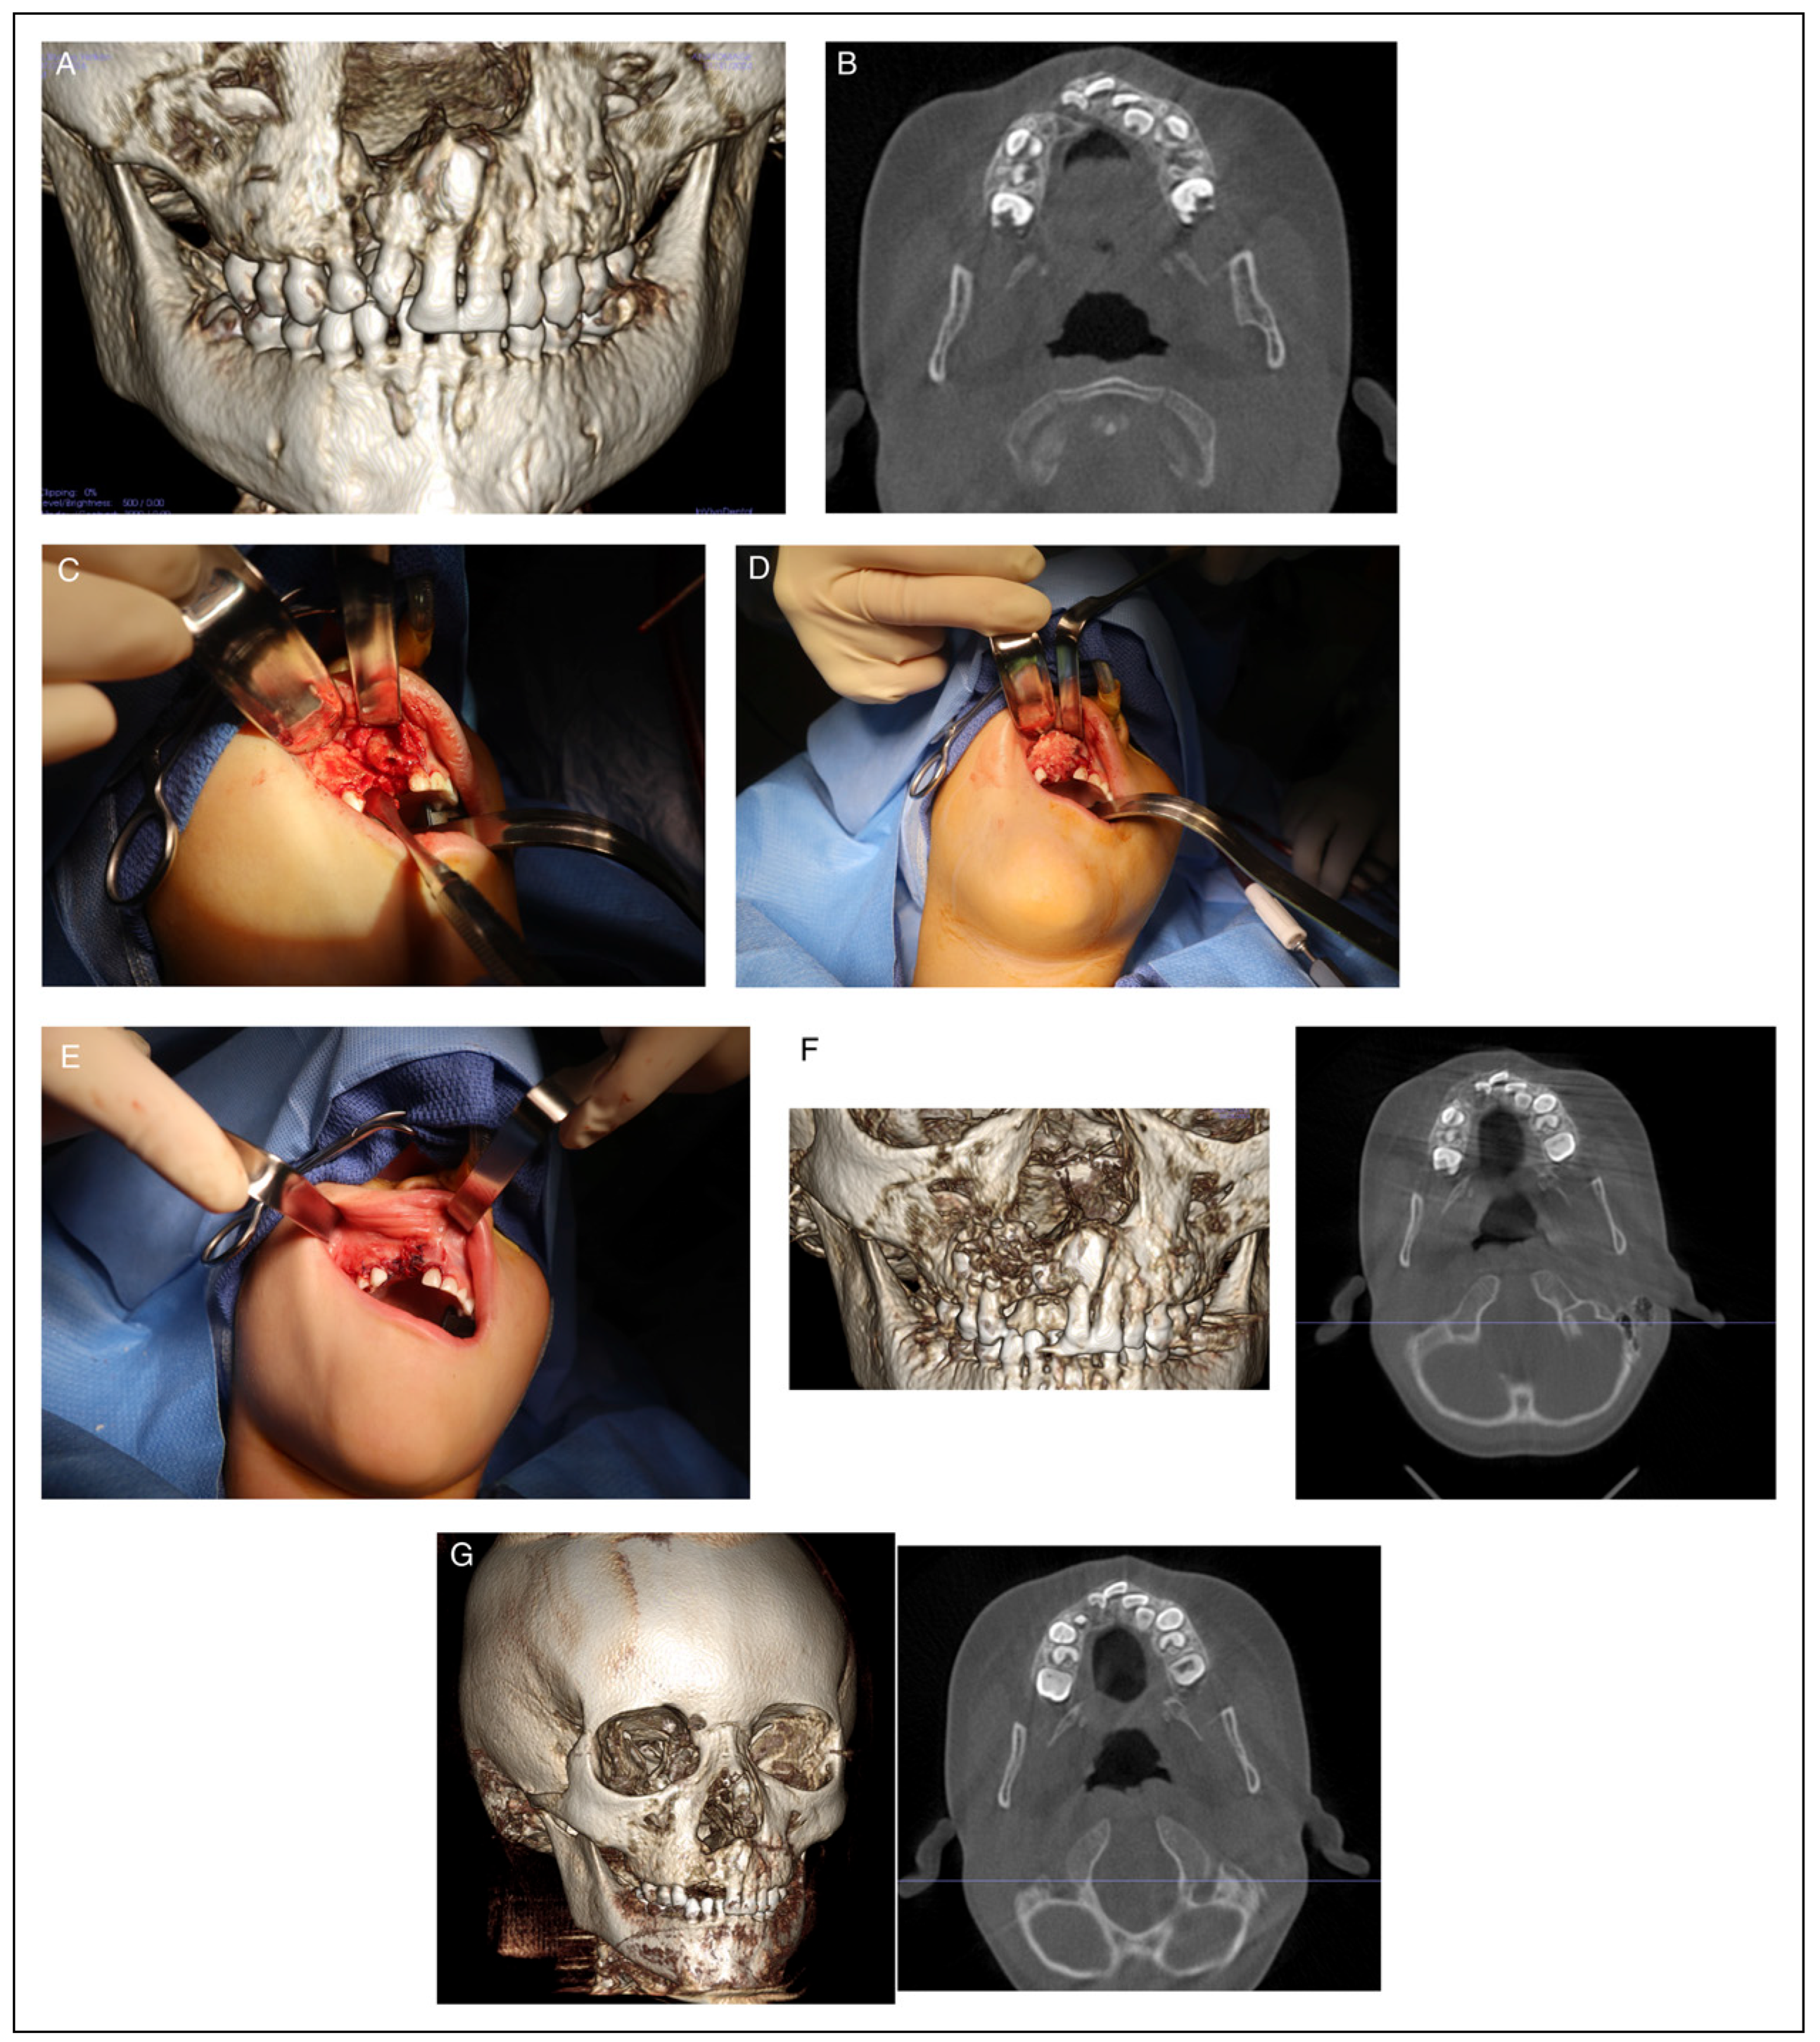

Reconstruction of Maxillary Bone Defects with Cellular Bone Matrix Allografts

Methods

Study Design and Sample

Results